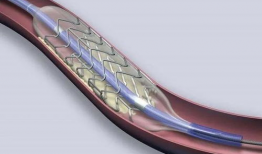

心脏支架手术视频,技术革新与患者康复之路

亲爱的读者,你是否曾好奇过心脏支架手术的全过程?想象当你躺在手术台上,医生们正小心翼翼地为你植入支架,那会是怎样的场景呢?今天,...